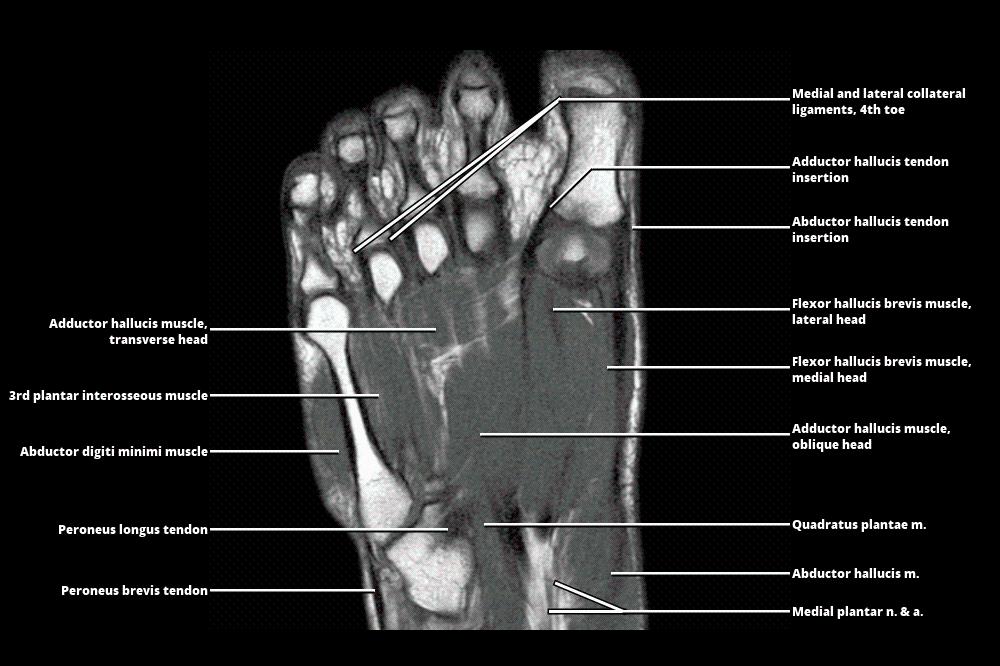

MRI - FOOT

www.wangmd.com

www.wangmd.com

mri atlas

MRI - FOOT

www.wangmd.com

www.wangmd.com

mri

MRI - FOOT

www.wangmd.com

www.wangmd.com

mri